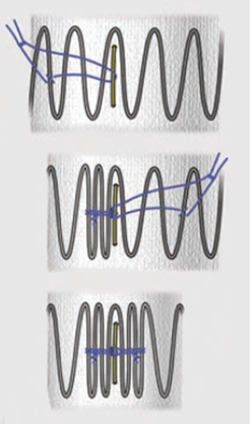

★ 开窗设计

开窗直径应略小于对应分支动脉;

利用金属环(定制/snare/弹簧圈)作为开窗标记;

如主动脉弓部扩张,可根据情况进行内/外分支缝合:内/外分支可为靶血管提供更大连接范围和安全性;

尽量追求开口的精准性;

膜上开口小于金属环直径,金属环直径小于桥接支架直径(例:7-8-9);

尽量使用电灼笔,而非锐性切割,否则容易造成开口过大或者出现意外裂痕。

★ 束径

束径只需要超过最远端开窗的1-2节即可;

束径尽量小,既要保证开口有一定的释放度,又要保证支架和主动脉之间存在选择空间(不贴壁);

合理束径可保证分支动脉有足够的灌注血流。